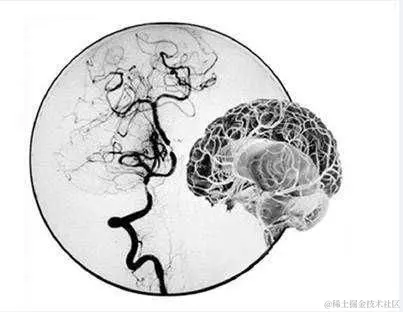

当我们听到“烟雾病”这个名字时,可能会联想到与吸烟有关的疾病,但实际上,这是一种与吸烟毫无关系的罕见脑血管疾病。它的名字来源于在脑血管造影中,病变的血管网看起来像一团乱麻,又似吸烟时吐出的烟雾。

烟雾病,又称脑底异常血管网病,是一种慢性进行性的脑血管疾病。它的主要特点是颈内动脉虹吸部及大脑前、中动脉起始部出现狭窄或闭塞,导致脑底出现异常的小血管网。这些异常的血管网在脑血管造影中呈现出烟雾状的影像,因此得名。

诊断烟雾病主要依赖于脑血管造影,这是一种通过向脑血管内注射造影剂,利用X线观察脑血管情况的检查方法。此外,头颅CT和MRI等影像学检查也有助于诊断。